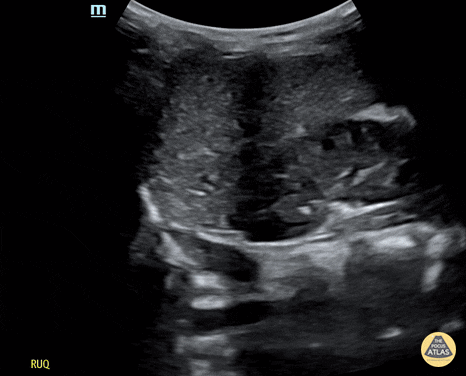

Trauma - Normal RUQ Evaluation

Normal RUQ on Efast of a 21-month-old male. Contributor: Jaron Smith, MD, Phoenix Children's Hospital